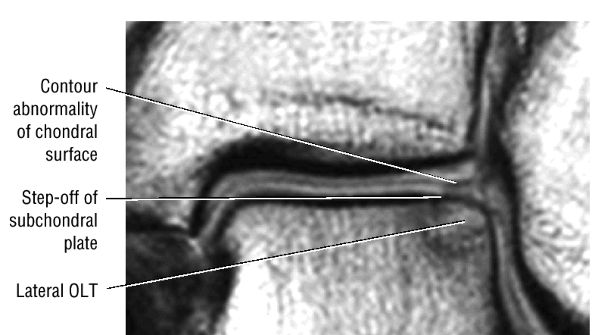

FIGURE 5.101 ● Contour irregularity of the chondral and subchondral plate and fracture extension to the talar surface in a stage II lesion with incomplete separation of the involved fragment. (A) Coronal T1-weighted image. (B) Coronal FS PD FSE image.